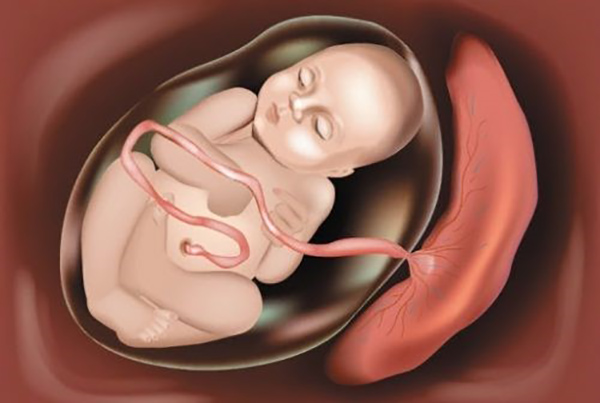

Trên thực tế, chúng ta không thể phủ nhận một số lợi ích của phương án sinh mổ. Nhưng bên cạnh những mặt lợi thì sinh mổ vẫn sẽ tồn tại các mặt có hại, đặc biệt là khi mẹ bầu sinh mổ lần 3. Sau đây sẽ là 5 mối nguy hiểm tiềm ẩn đối mà mẹ bầu và bé cưng có thể gặp phải khi sinh mổ lần 3.

Nhau thai có sự bất thường

So với dính ruột, việc nhau thai xuất hiện sự bất thường sẽ thường xảy ra hơn. Lí do là vì mẹ đã sinh mổ nhiều lần, khiến tử cung có sẹo. Những vết sẹo này là một trong những tác nhân chủ yếu khiến nhau tiền đạo, nhau bong non. Thậm chí, đã từng có trường hợp nhau cài răng lược kèm theo các biến chứng nguy hiểm cho mẹ như băng huyết sau sinh hoặc phải cắt bỏ tử cung để cứu mẹ.

Nứt hoặc vỡ tử cung

Đối với mẹ bầu sinh mổ lần 3 mà nói, việc nứt hoặc vỡ tử cung là một điều cực kỳ nguy hiểm. Thế nhưng, xác suất nứt hoặc vỡ tử cung đối với các mẹ bầu sinh mổ lại cao hơn mẹ bầu sinh mổ lần 1 và lần 2 rất nhiều. Nguyên nhân gây nên tình trạng nứt hoặc vỡ tử cung này chủ yếu là do vết sẹo cũ của hai lần sinh mổ trước đó.

Khi cổ tử cung của mẹ có những vết sẹo này, các cơ có trên thành tử cung sẽ yếu hơn bình thường. Thế nên, khi tử cung của mẹ co thắt chuẩn bị vượt cạn thì xác suất các vết sẹo này bị bục là rất cao.

Khi đó, tử cung của mẹ sẽ bị nứt, thậm chí là bị vỡ gây nguy hiểm cho cả mẹ và bé cưng. Có thể nói, tình trạng nứt hoặc vỡ tử cung là tình trạng nguy hiểm nhất và cũng là điều khiến nhiều mẹ bầu lo ngại nhất khi có ý định hoặc được bác sĩ chỉ định sinh mổ lần 3.